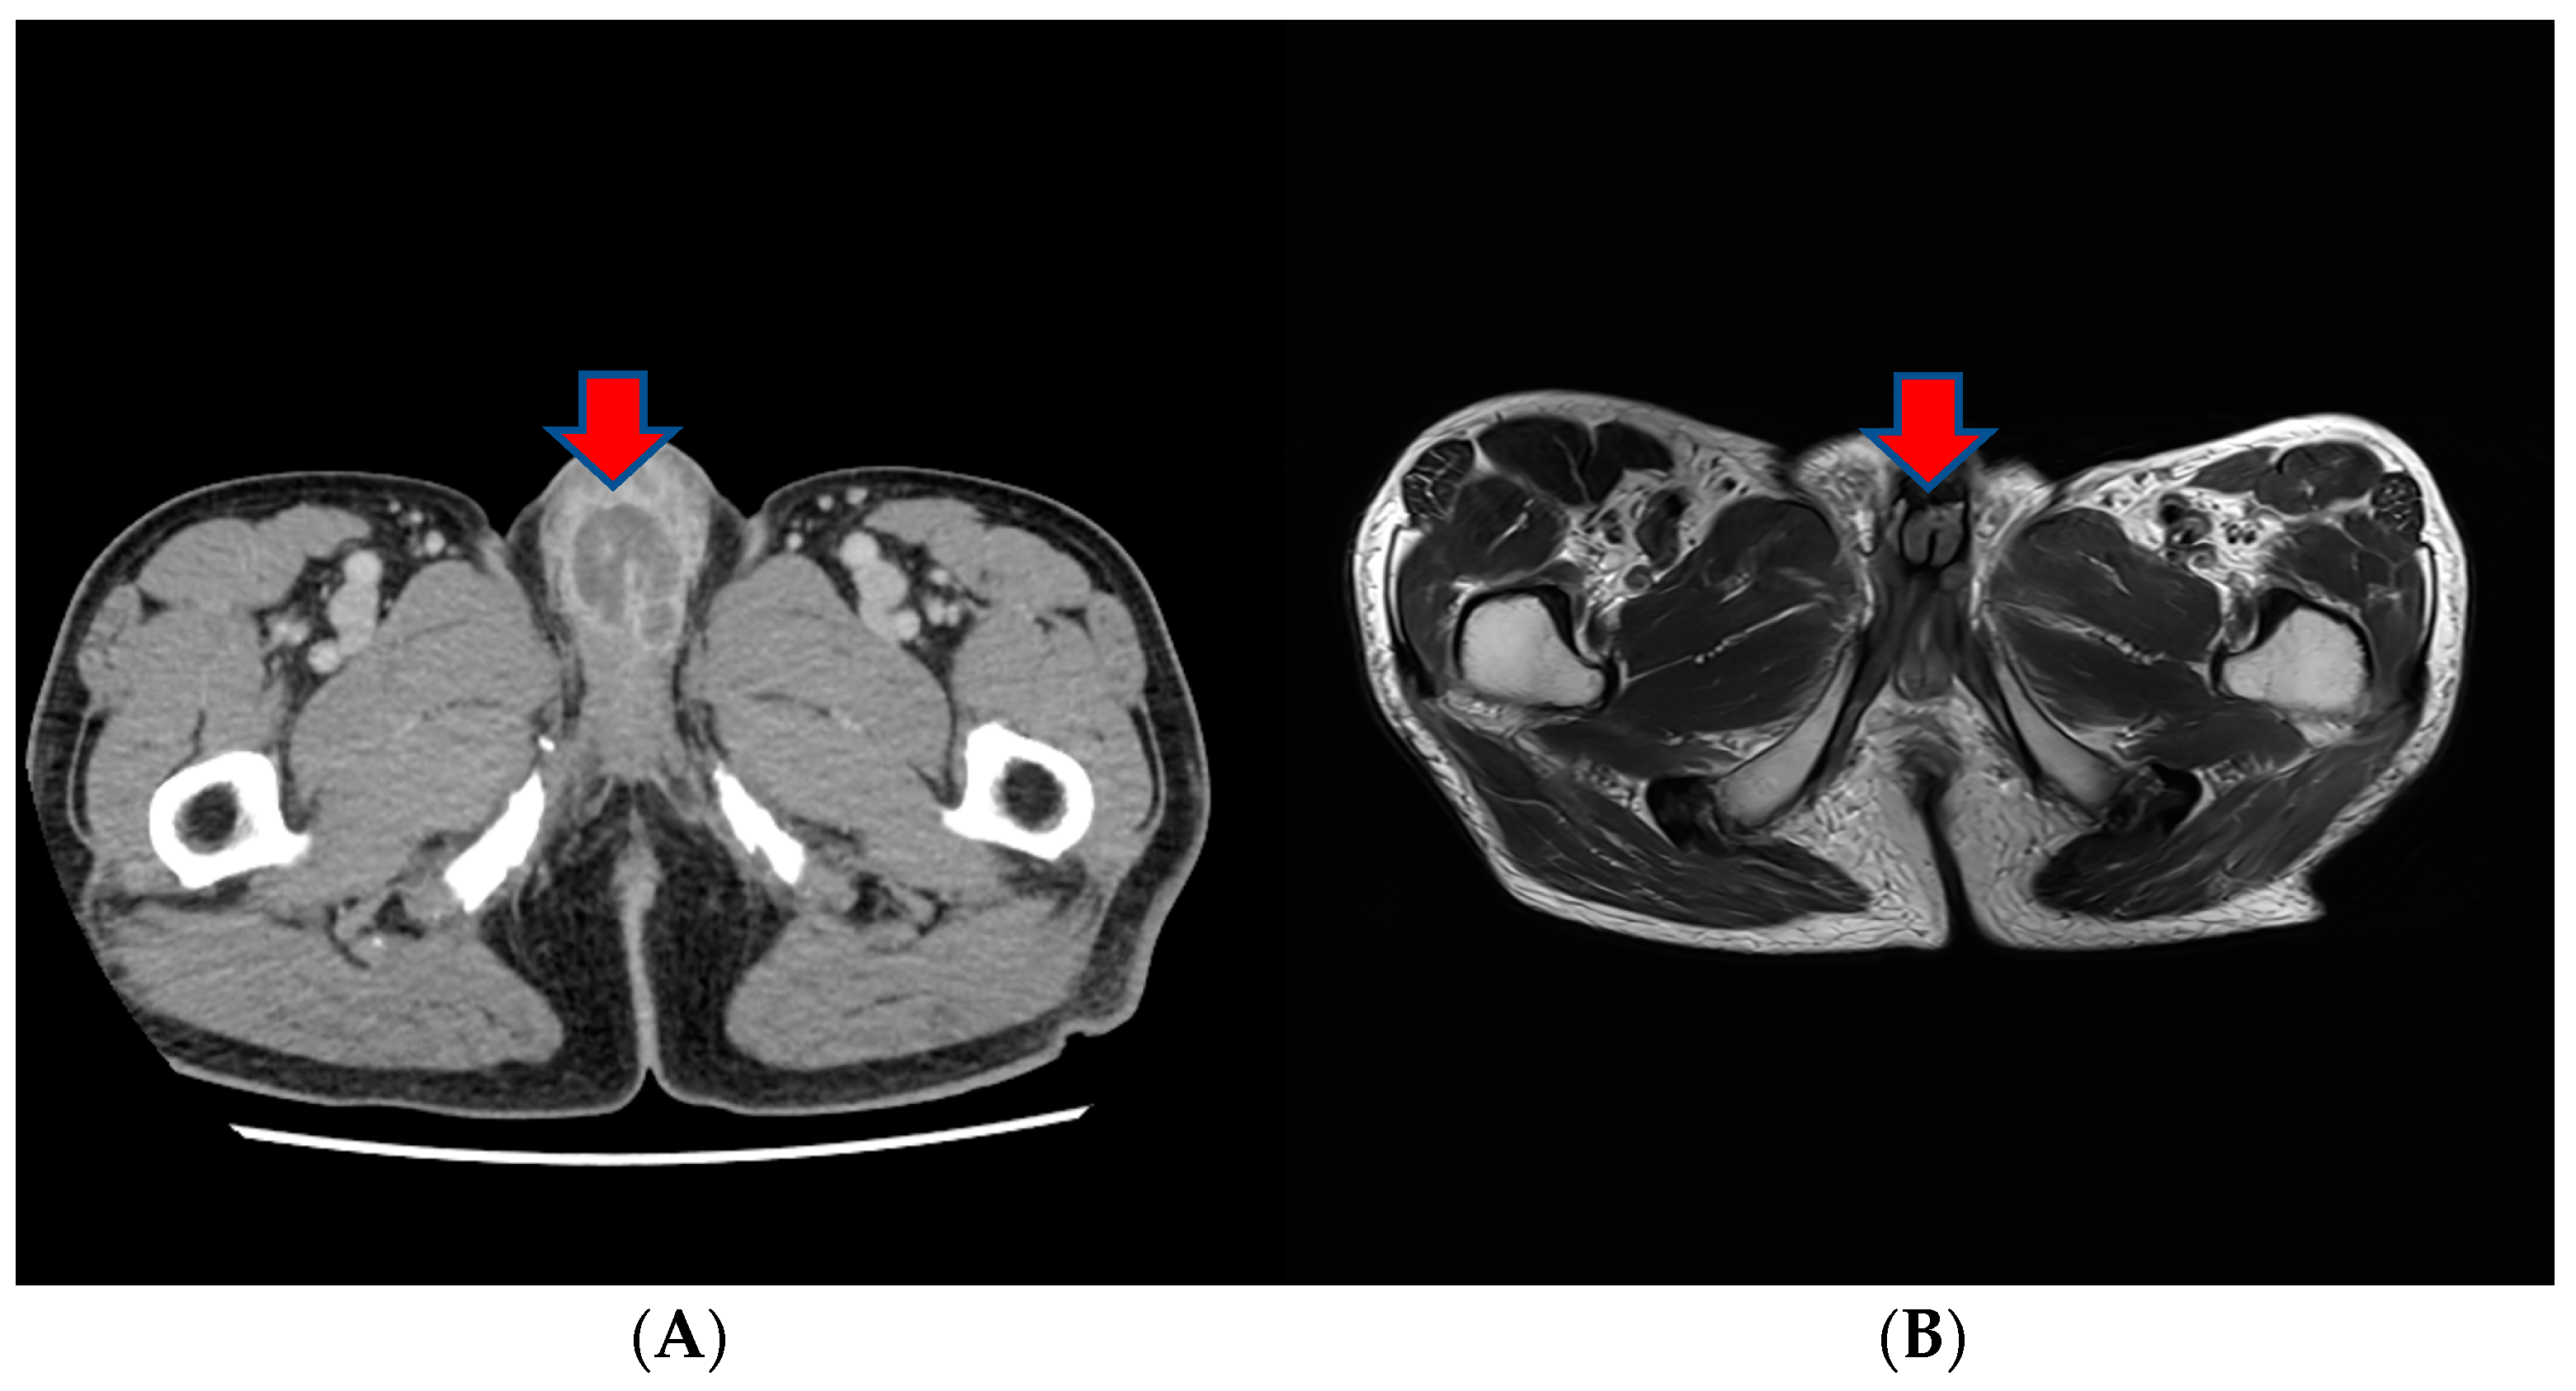

About a month after the surgical procedure, the patient began experiencing penile discomfort, which worsened over three months, prompting his hospital visit. Upon physical examination, a palpable mass was detected at the penoscrotal junction of the penis. The mass was tender, firm in consistency without ulcerations or rash, and measured approximately 5 cm in diameter. No other abnormalities were noted during the examination of the genitalia. Subsequent to this, a CT scan revealed an irregularly shaped enhancing mass in the penis, suggesting the possibility of metastasis (Figure 3). Laboratory results were within normal ranges. On urinalysis, pyuria was observed, but the urine culture showed no microorganism. Magnetic resonance imaging (MRI) findings revealed a lobulated contour and heterogeneously enhanced mass-like lesion in the corpus cavernosa of the penis on T2-weighted images, which raised the possibility of metastasis (Figure 3). A PET-CT showed an irregular increased fludeoxyglucose (FDG) uptake in the penis (Figure 3).

However, in a subsequent CT scan performed approximately 4 months later, an increased size of the mass in the penis was observed, and persistent penile pain led to the consideration of radiation therapy (Figure 4). After radiation therapy, a follow-up CT scan showed a decreased tumor size (5.1 cm to 3.4 cm) (Figure 4).

Figure 4.

(A) A subsequent CT scan performed approximately 4 months later showing an increased size of the mass in the penis. (B) After radiation therapy, a follow-up CT scan showed the decreased size of the tumor.